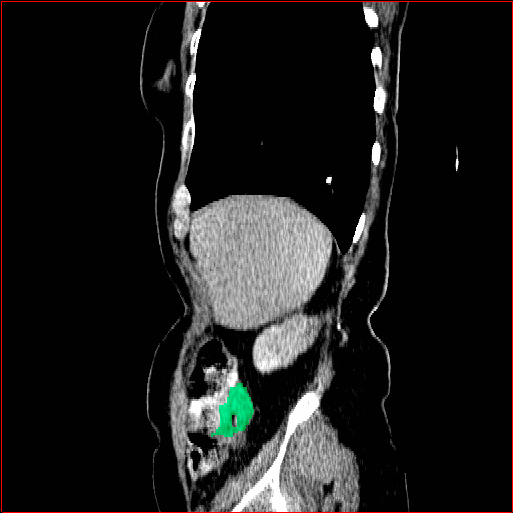

Panc. Tumor

1×1×11\times 1\times 1

mm

512×512×512512\times 512\times 512

Refer to caption

Figure 5: MAISI-v2 segmentation-guided results for five types of tumors. We show results for different voxel spacing and volume size to demonstrate the flexibility of MAISI-v2. Different Hounsfield Unit window is used to better show the contrast between tumor and normal tissues.